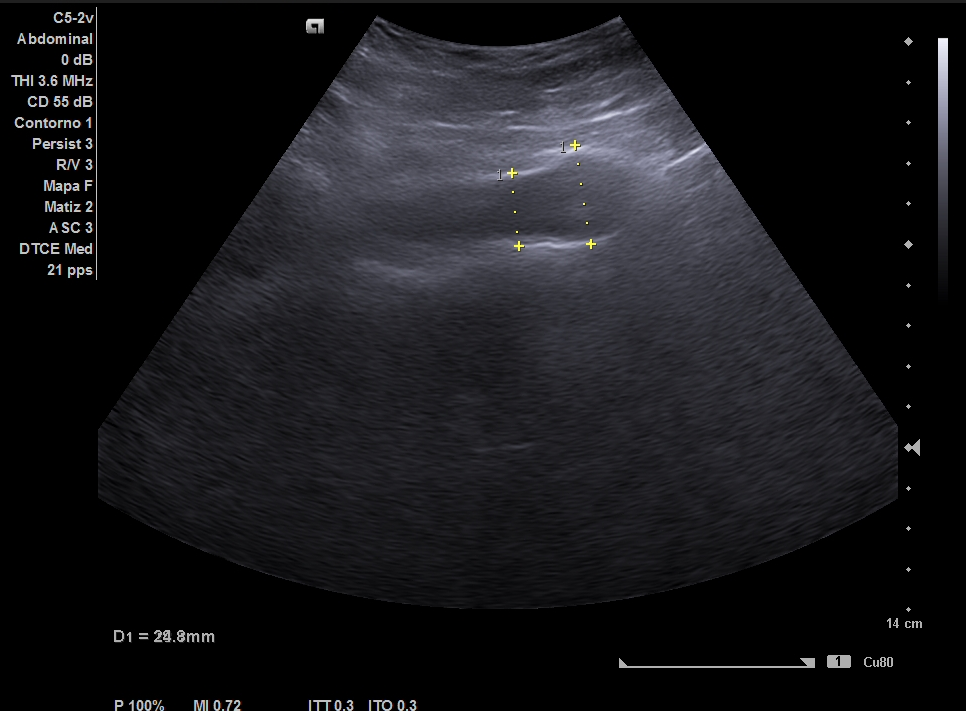

Parenquima hepatico sin alteraciones, vesícula biliar sin imagenes hiperecoénicas en interior. Pancreas visible en parte, sin alteraciones. Asimetría entre ambos riñones compatible variante de la normalidad RI. Llama la atención dilatación ilíaca derecha al comparar con contralateral y con aorta abdominal distal. Compatible con dilatación aneurismática ilíaca derecha.

El diagnóstico diferencial del Aneurisma Ilíaca con: Displasia fibromuscular u otra patología del tejido conectivo, lúes o tuberculosis entre otros. Toda dilatación que sobrepase el 50% del diámetro del vaso se considera aneurismática. Por la edad no se plantea el origen ateromatoso.

La ecografía en Atención Primaria se plantea en el contexto de responder a una pregunta clínica tras la anamnesis y la exploración física u otras pruebas complementarias que se precisen. A resaltar, la importancia de realizar ecografía completa siguiendo una sistemática y prestando atención tanto a variantes de la normalidad como a hallazgos patológicos. En el caso de la ecografía abdominal, es fundamental explorar los grandes vasos tanto en plano transversal como longitudinal, haciendo incapié en la división de las ilíacas.